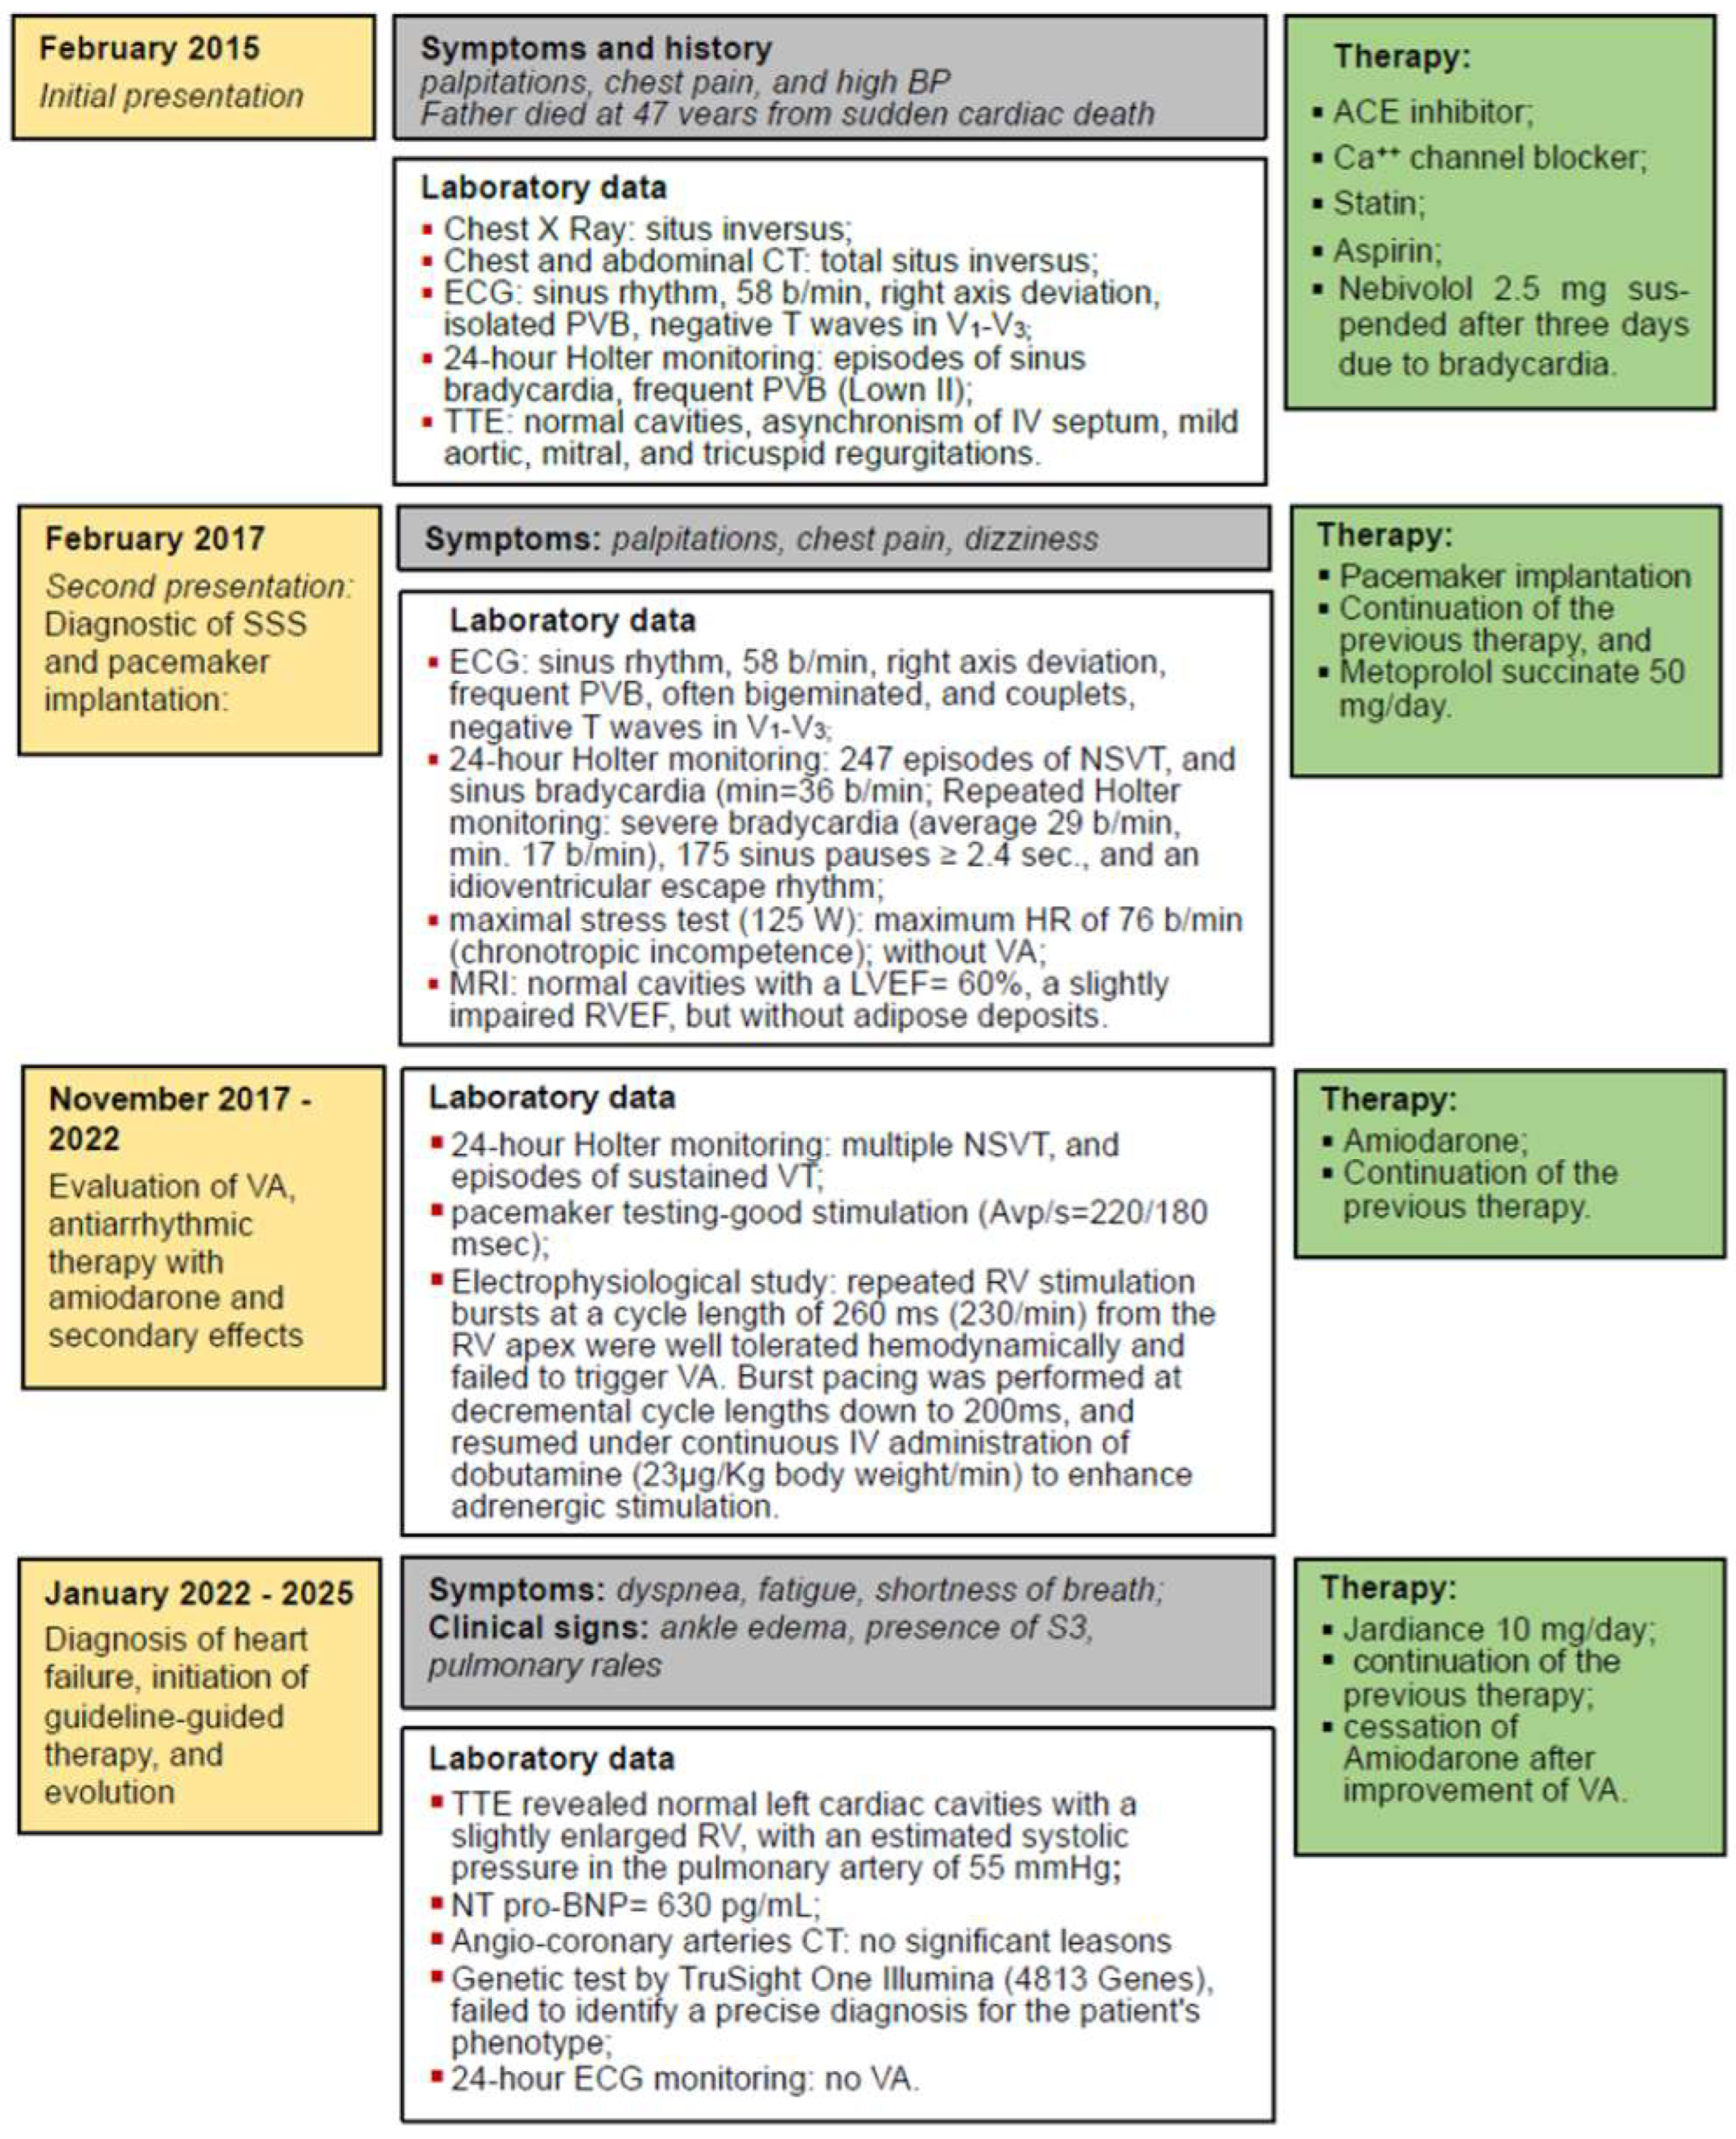

2.1. Initial Presentation

2.2. Diagnostic of SSS and Pacemaker Implantation

2.3. Evaluation of VA, Antiarrhythmic Therapy with Amiodarone and Secondary Effects

2.4. Diagnosis of Heart Failure, Initiation of Guideline-Guided Therapy, and Evolution